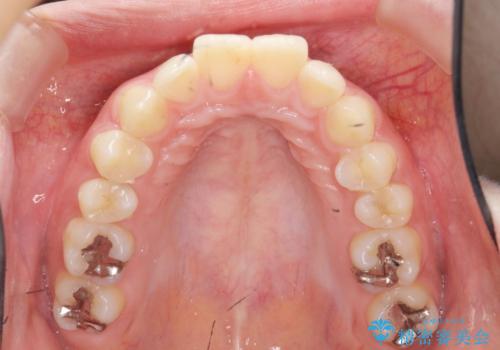

カリエール・マイクロインプラントを併用した歯の突出を改善する大きな遠心移動

- 口が閉じづらく、突出し歯が出っ歯に見えてしまうことの改善を求めて来院されました。

通常このような場合、抜歯してのワイヤー矯正治療も選択肢に入りますが、患者様の強い希望により抜歯を行わずマウスピースによる治療を選択しました。

カリエール・マイクロインプラントを用い、時間はかかりましたが大きく歯の後方移動が達成され、前歯の見た目が大きく改善されました。